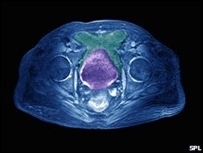

"Este é o primeiro teste clínico de fase 3 que mostra que bloquear a formação de vasos sanguíneos dos tumores melhora consideravelmente a sobrevivência sem o desenvolvimento da doença das mulheres com câncer de ovário ou peritoneal, muito difícil de tratar", explicou Robert Burger, médico do Fox Chase Cancer Center, na Filadélfia, que chefiou a pesquisa.

"Os resultados do teste clínico mostram que o Avastin é um fármaco inicial aceitável para as pacientes que sofrem de câncer avançado de ovário", acrescentou, ao apresentar os resultados na conferência anual da Sociedade Americana de Oncologia Clínica, reunida este fim de semana em Chicago.

O Avastin, comercializado pela empresa americana Genentech, que faz parte do grupo farmacêutico suíço Roche, já foi autorizado pela FDA (Agência de Alimentos e Medicamentos) dos EUA para o tratamento de vários cânceres metastásicos, entre eles os de cólon, seio, rim, cérebro e pulmão.